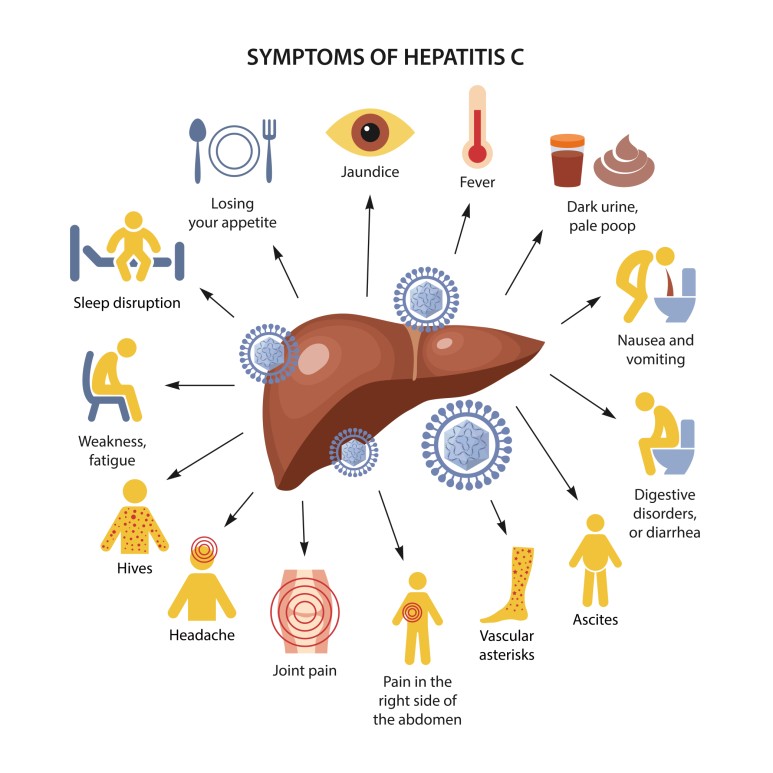

담관이 폐쇄되면 간에도 영향을 미칩니다.

담관주위 담즙유출, 문맥주위염증, 담관확장, 담전형성 등으로 간조직에 변화가 발생합니다.

시간의 흐름에 따라 담즙에 의한 간경화가 발생할 수 있으므로 주의하시기 바랍니다.

담즙성 간경변이 발생할 경우 담관의 압력을 낮추려고 담관의 배액을 수행해도 간경변이 유지되는 비가역적 변화가 발생할 수 있습니다.

이로 인해 담관염이 빈번하게 발생하여 간농양도 발생할 수 있으므로 주의해 주십시오.

담관폐쇄로 인해 담즙이 정체되어 있는 경우 세균증식이 자주 이루어지며 담관염이 발생합니다.담석으로 막혔을 때 흔히 발생하며 담석에 세균이 많이 분포되어 있어 부분적으로 폐쇄되는 경우 사이를 통해 세균이 담관 상부로 유입될 수 있기 때문입니다.

악성에 의한 담관 폐쇄에는 담관염의 발생이 드물지만 폐쇄가 장시간 계속되면 발생할 가능성이 있습니다.

담관이 폐쇄가 되면 심장에도 영향을 미칠 수 있을 것 같습니다.

좌심실 기능의 감소 및 서맥, 혈관 저항의 감소가 발생할 수 있습니다.

또 다른 문제로는 혈중 담즙산이 증가하면 이로 인해 이뇨작용이 발생하게 되며 신장의 혈관수축, 저혈압과 같은 문제가 발생하여 신부전 발생 위험이 증가하게 됩니다.

고빌리루빈혈증 시 신장 수질이 손상될 수 있으며, 특히 신생아에게 발생하는 핵 황달과 같은 경우 간접빌리루빈 농도가 높으면 자주 발생하여 뇌세포 손상까지 발생할 수 있으므로 주의해야 합니다.

성인의 경우 높은 빌리루빈 혈증이 계속되어도 뇌 손상은 발생하지 않습니다.

면역기능에 문제가 생겨 숙주 방어기능이 저하되어 패혈증의 위험이 증가될 수 있습니다.